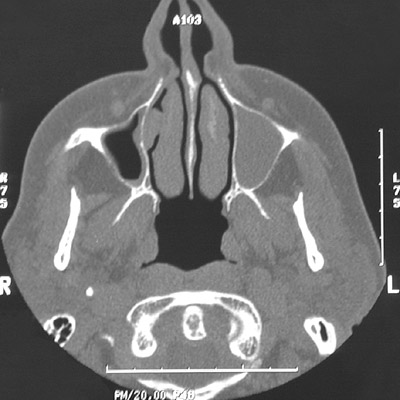

| Compared to the air-filled maxillary sinus on the right, the CT scans of the head above and below demonstrate a uniform gray appearance to the left maxillary sinus as a result of the collection of mucoid secretions following inflammation and stricture of the small duct draining the sinus. This is a mucocele that is expanding the sinus and thinning the surrounding bone. A mucus retention cyst from a blocked minor mucus gland in the paranasal sinus will appear similarly. |